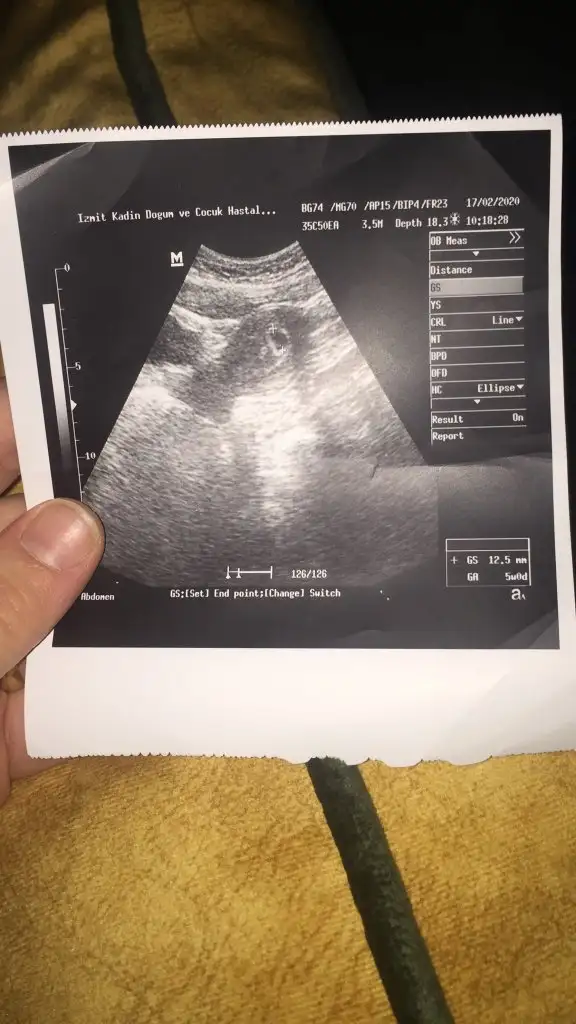

Canım dr sor istersen kesen ne kadar küçük 5 haftalık dı demi ben bugün gittim kesem ilkine göre baya büyümüştü dr göre 7+6 gün çıkıyoKızlar kesenin sol altında birşey var lütfen anlayan yazabilirmi

Bakalım yarın tekrar gıdıcem sorarımBelki küçük kist tir benimde vardı ona benzettim geçti bebek büyüdükçe o